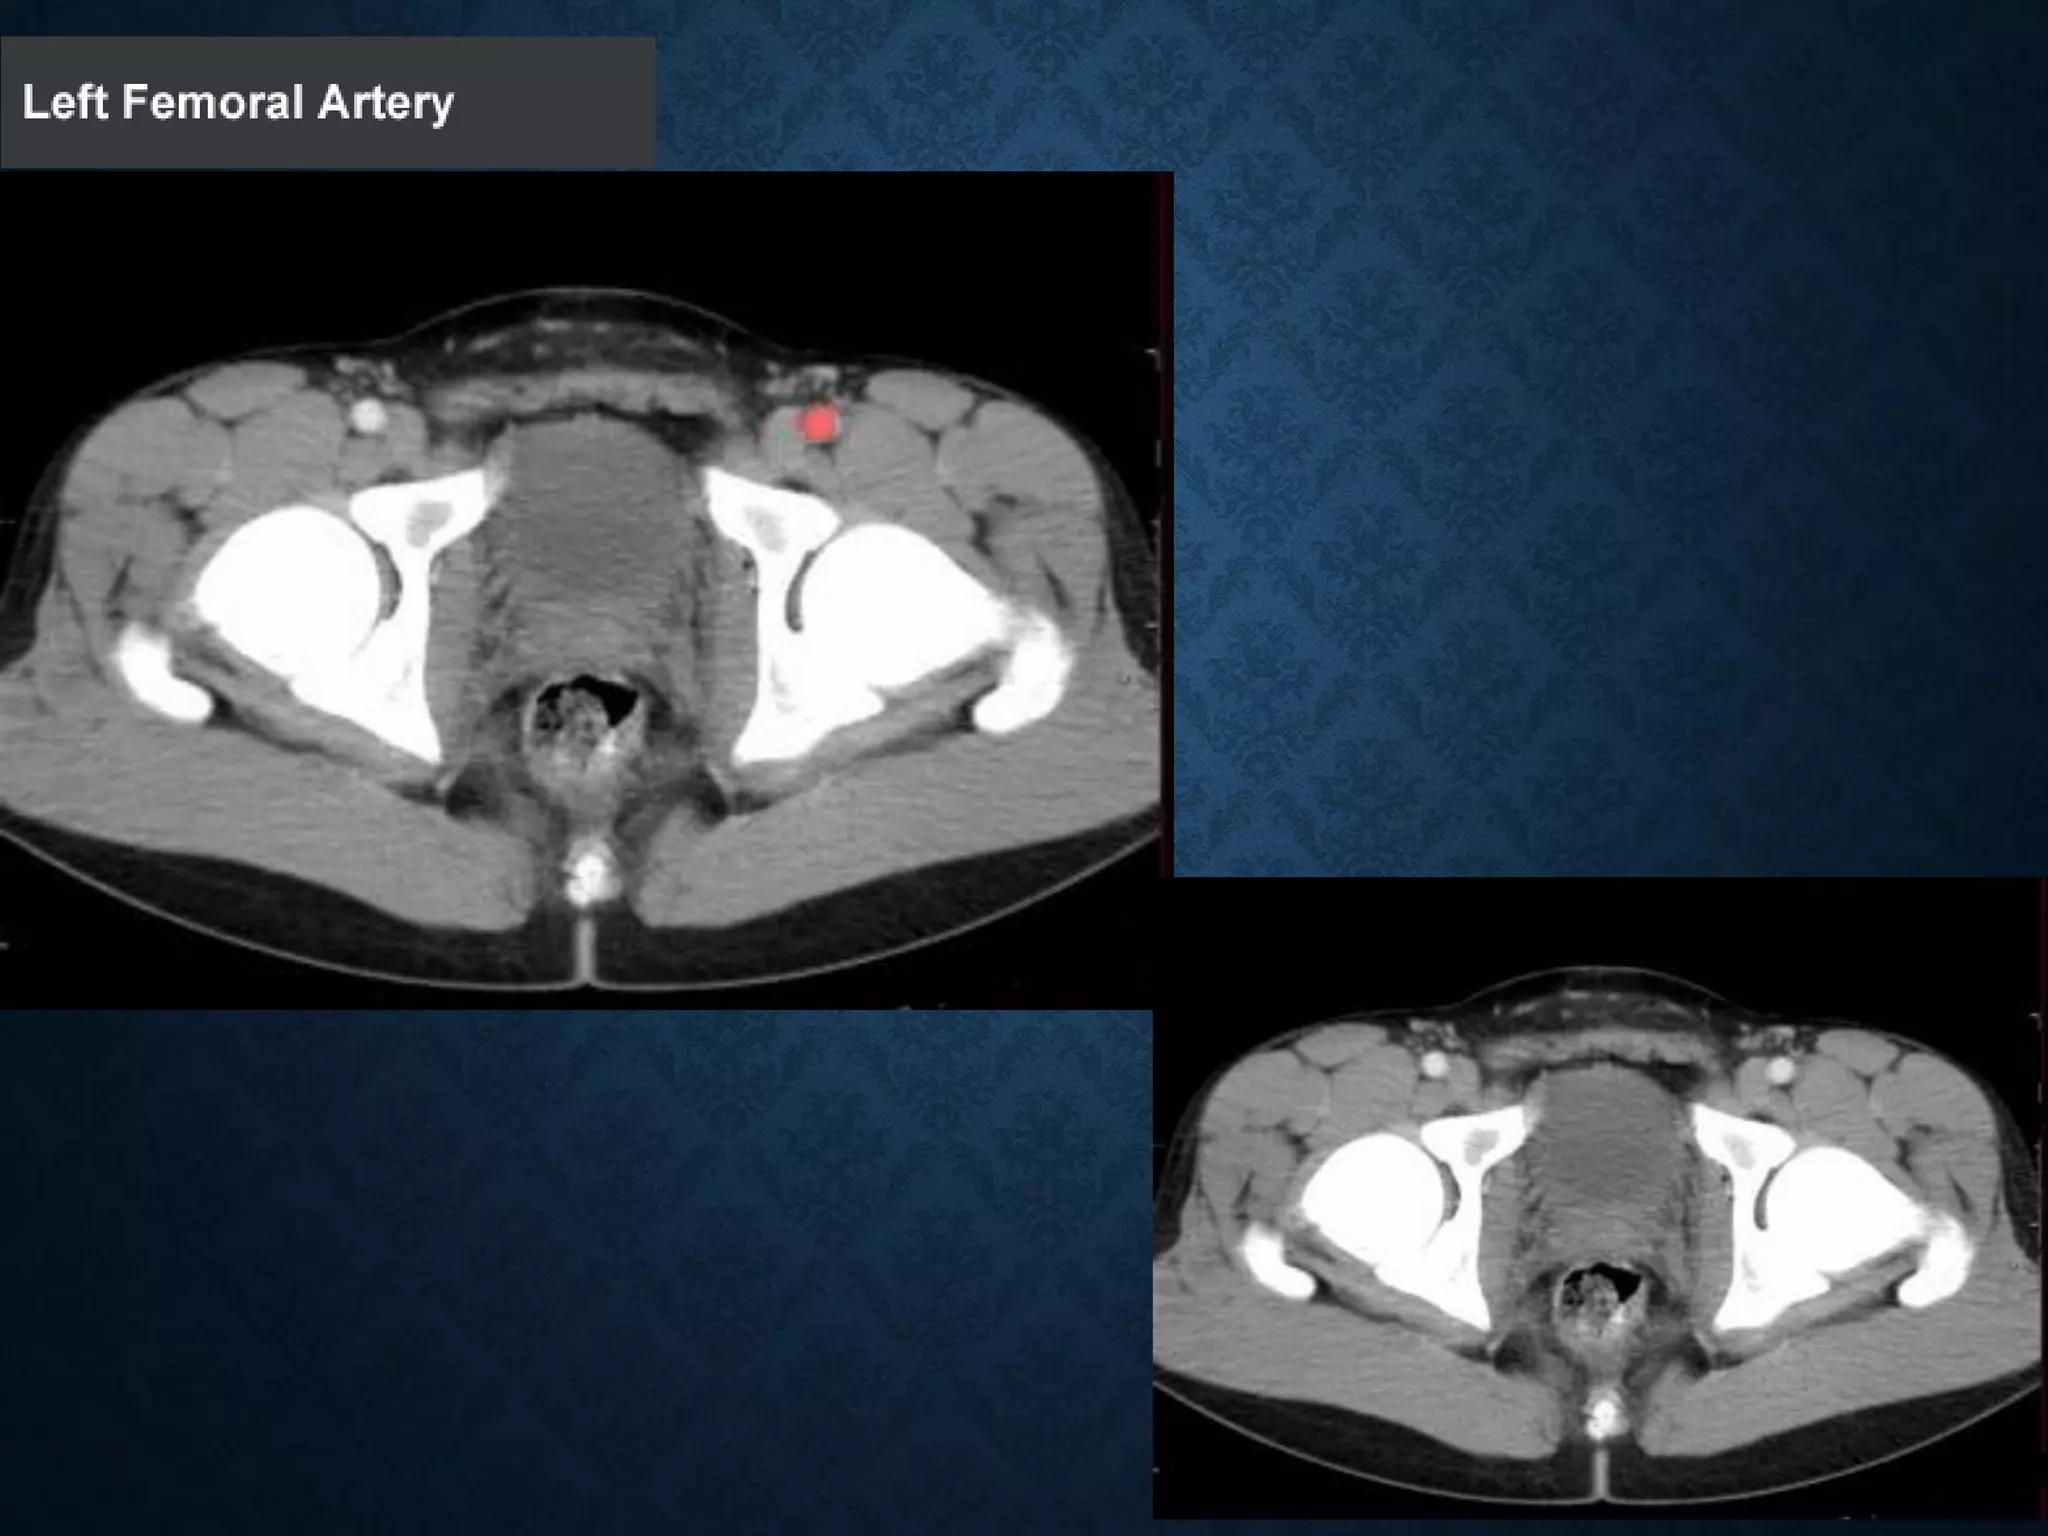

Identify the following structures in the body CT to the right. To view the location of the structure in the image click on

the label at the left and the structure will be indicated in the image. Abdominal CT scans typically begin just above

the diaphragm, so the first slice you see is of the lower chest.

INGUINAL LIGAMENT